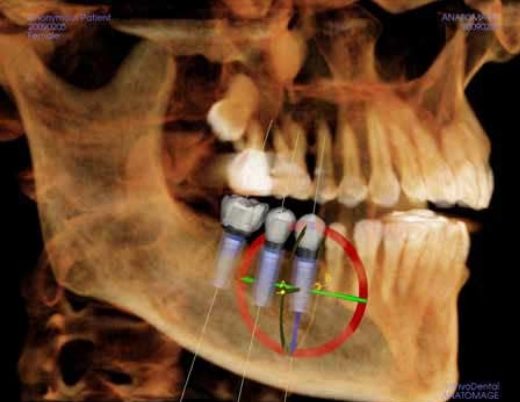

Cone Beam Computed Tomography (CBCT) is the most advanced type of dental x-ray and is available in very few clinics. The image produced is in 3 dimensions. In the above example, it is used in the precise planning of implant placement.